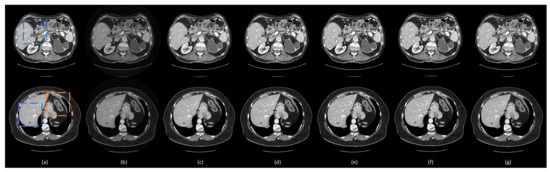

3.3. Comparison with Other Deep Learning Methods

3.4. Ablation Analysis